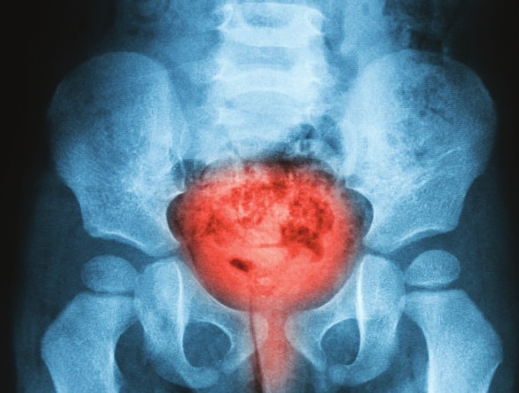

Hematuria(Blood in

the urine) Many women are rightly referred for evaluation of hematuria

(blood in the urine). Most people are not even aware of the presence

of blood, as it is subtle enough not to cause an actual change in urine

color. A few tests are needed to determine if the cause is serious or

not. This usually includes imaging of the kidney (either with

ultrasound or CT) and a scope of the bladder. The outcome is most often

negative, but occasionally will lead to a major diagnosis like bladder

or kidney cancer.